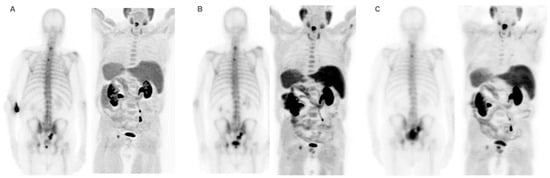

According to the analysis of baseline parameters of imaging techniques, only a single patient did not undergo a baseline BS prior to treatment, while 87 underwent a baseline FCH PET/CT. All patients showed a positive BS and FCH PET/CT scan. Additionally, a high tumor burden was observed in 61% of BS and 48% of FCH PET/CT. Furthermore, FCH PET/CT detected STI in sixteen patients, fourteen with nodal involvement, three with local prostatic disease, and prostatic and nodal disease in two patients. The detailed analysis of baseline parameters derived from the results of these techniques is described in Table 1 and Table 3.

Performance status before 223Ra (p < 0.001), AP baseline levels (p < 0.001), and LDH (p = 0.033) were found to have a significant impact on OS (Figure 1), as well as other factors such as completion of treatment with 223Ra (p < 0.001). Regarding imaging variables, both the chi-square and the log-rank tests showed that derived FCH PET/CT variables had statistical significance. Thus, high tumor burden (p = 0.003), uptake of the most hypermetabolic lesion above the liver (p < 0.001), or STI in the FCH PET/CT study (p = 0.048) were associated with a lower median OS (Figure 2). Focusing on treatment response assessment, only interim studies (BS and FCH PET/CT) showed a significant association with OS, with data extracted from FCH PET/CT being slightly more robust compared to BS (p < 0.001 vs. p = 0.004, respectively) (Figure 3). The significant variables in the univariate analysis were included in the multivariate analysis for the OS and therapeutic failure end-points. In the former, the association of uptake of BM above the liver (p = 0.011), therapeutic failure (p = 0.001), or pathological baseline AP (p = 0.011) was highlighted as leading to lower OS. Table 8 details the results of the univariate Cox regression, and Table 9, Table 10 and Table 11 show the results of the log-rank test regarding OS.

Given the similar uptake properties of 223Ra and BS tracer in osteoblastic bone, a reasonable hypothesis is that metastatic disease with higher uptake on BS or 18F-NaF PET/CT compared to FCH PET/CT, is more likely to respond to 223Ra therapy, based on that increased choline levels can reflect on more aggressive tumors [39,40,41,42,43,44,47,48]. Ahmadzadehfar et al. [49] reported that when PSMA PET/CT is used as the gatekeeper in addition to BS, radionuclide therapy with 223Ra might be more effective and have more success regarding changes in the PSA, mainly because of better patient selection with the exclusion of patients with bone marrow involvement or STI. In our case, similar results were found with the combined use of FCH PET/CT and BS, as some of the FCH PET/CT variables had significant associations with OS. These included bone marrow infiltration (median 6 vs. 14 months; p < 0.001), uptake of the most hypermetabolic BM above the liver (median 10.5 vs. 16 months; p < 0.001), and STI (median 7 vs. 14 months; p = 0.048).

Figure 2. Kaplan–Meier OS curves of baseline FCH PET/CT radiomics: high tumor burden (upper left panel), uptake higher than liver for the most hypermetabolic bone metastases (upper right panel), bone marrow involvement (lower left panel), and soft tissue involvement (lower right panel).

Cancers 16 02695 g002